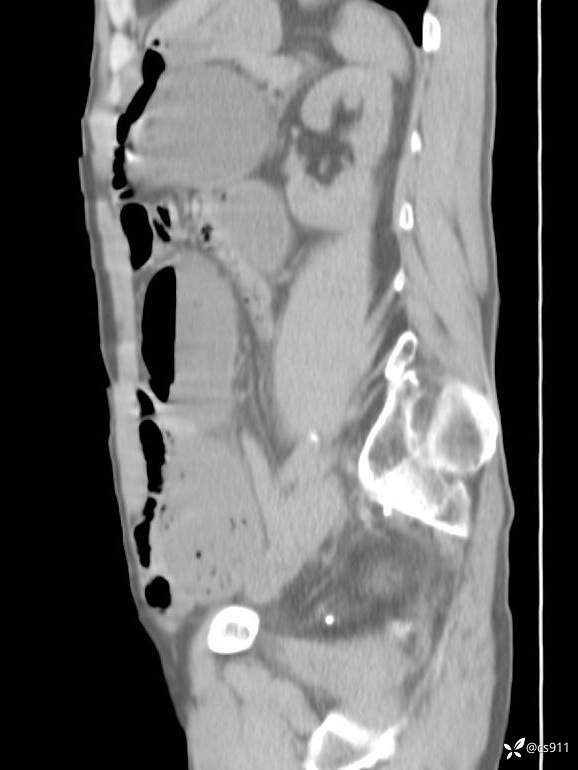

急腹症之急诊CT,原因?答案公布

男,77岁,腹痛、腹胀伴恶心呕吐1天。呕吐胃内容物,非喷射性呕吐,有咖啡色样胃内容物,诉有胃穿孔病史。查体:全腹平,下腹部压痛,全腹无反跳痛,叩诊呈浊音,移动性浊音阴性,肠鸣音减弱,1-2次/分。肛检:直肠未扪及明显肿物,可触及大量粪块。

血淀粉酶(AMY) HH 1859 U/L 35-135